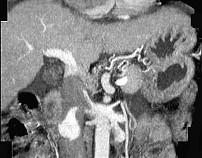

问题 女性,55岁,曾患乙肝,肝硬化多年,右上腹胀痛1月余,CT检查如图所示,最可能的诊断是 ( )

选项 A.肝硬化腹水、下腔静脉血栓形成 B.肝硬化腹水、胆管细胞癌 C.肝硬化腹水、肝癌并下腔静脉癌栓 D.肝硬化腹水、肝脓肿 E.肝硬化腹水、肝血管瘤

答案 C